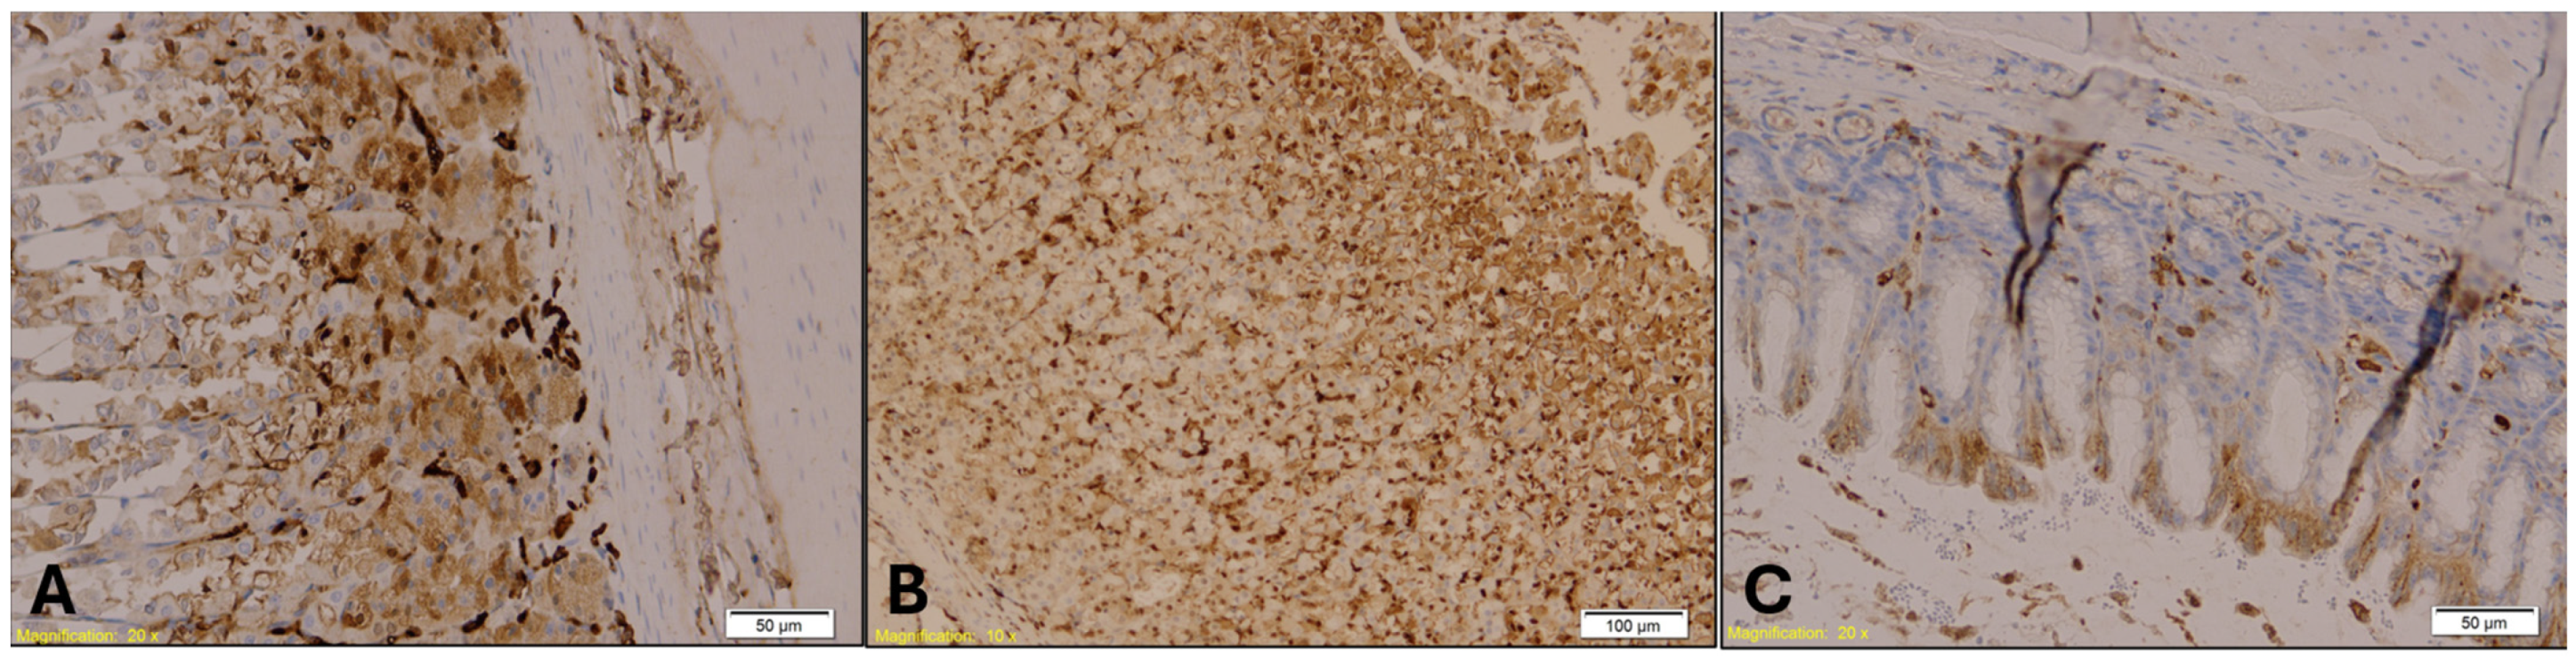

- E-cadherin (mouse monoclonal, 1:200)—Kidney: E-cadherin is a transmembrane protein involved in epithelial cell adhesion and polarity. Its expression is typically preserved in distal renal tubules but reduced in proximal segments. Loss or reduction in E-cadherin staining may reflect epithelial stress or ischemic injury, making it a useful marker for assessing hypothermia-induced renal damage.

- Myeloperoxidase (MPO) (rabbit monoclonal, 1:100)—Lung and Spleen: MPO is a non-specific marker of neutrophilic infiltration and oxidative stress. It is used to evaluate inflammatory responses and immune activation, which may be altered in hypothermia and further modulated by alcohol or benzodiazepine exposure.

| E-cadherin | Epithelial cadherin |

| MPO | Myeloperoxidase |